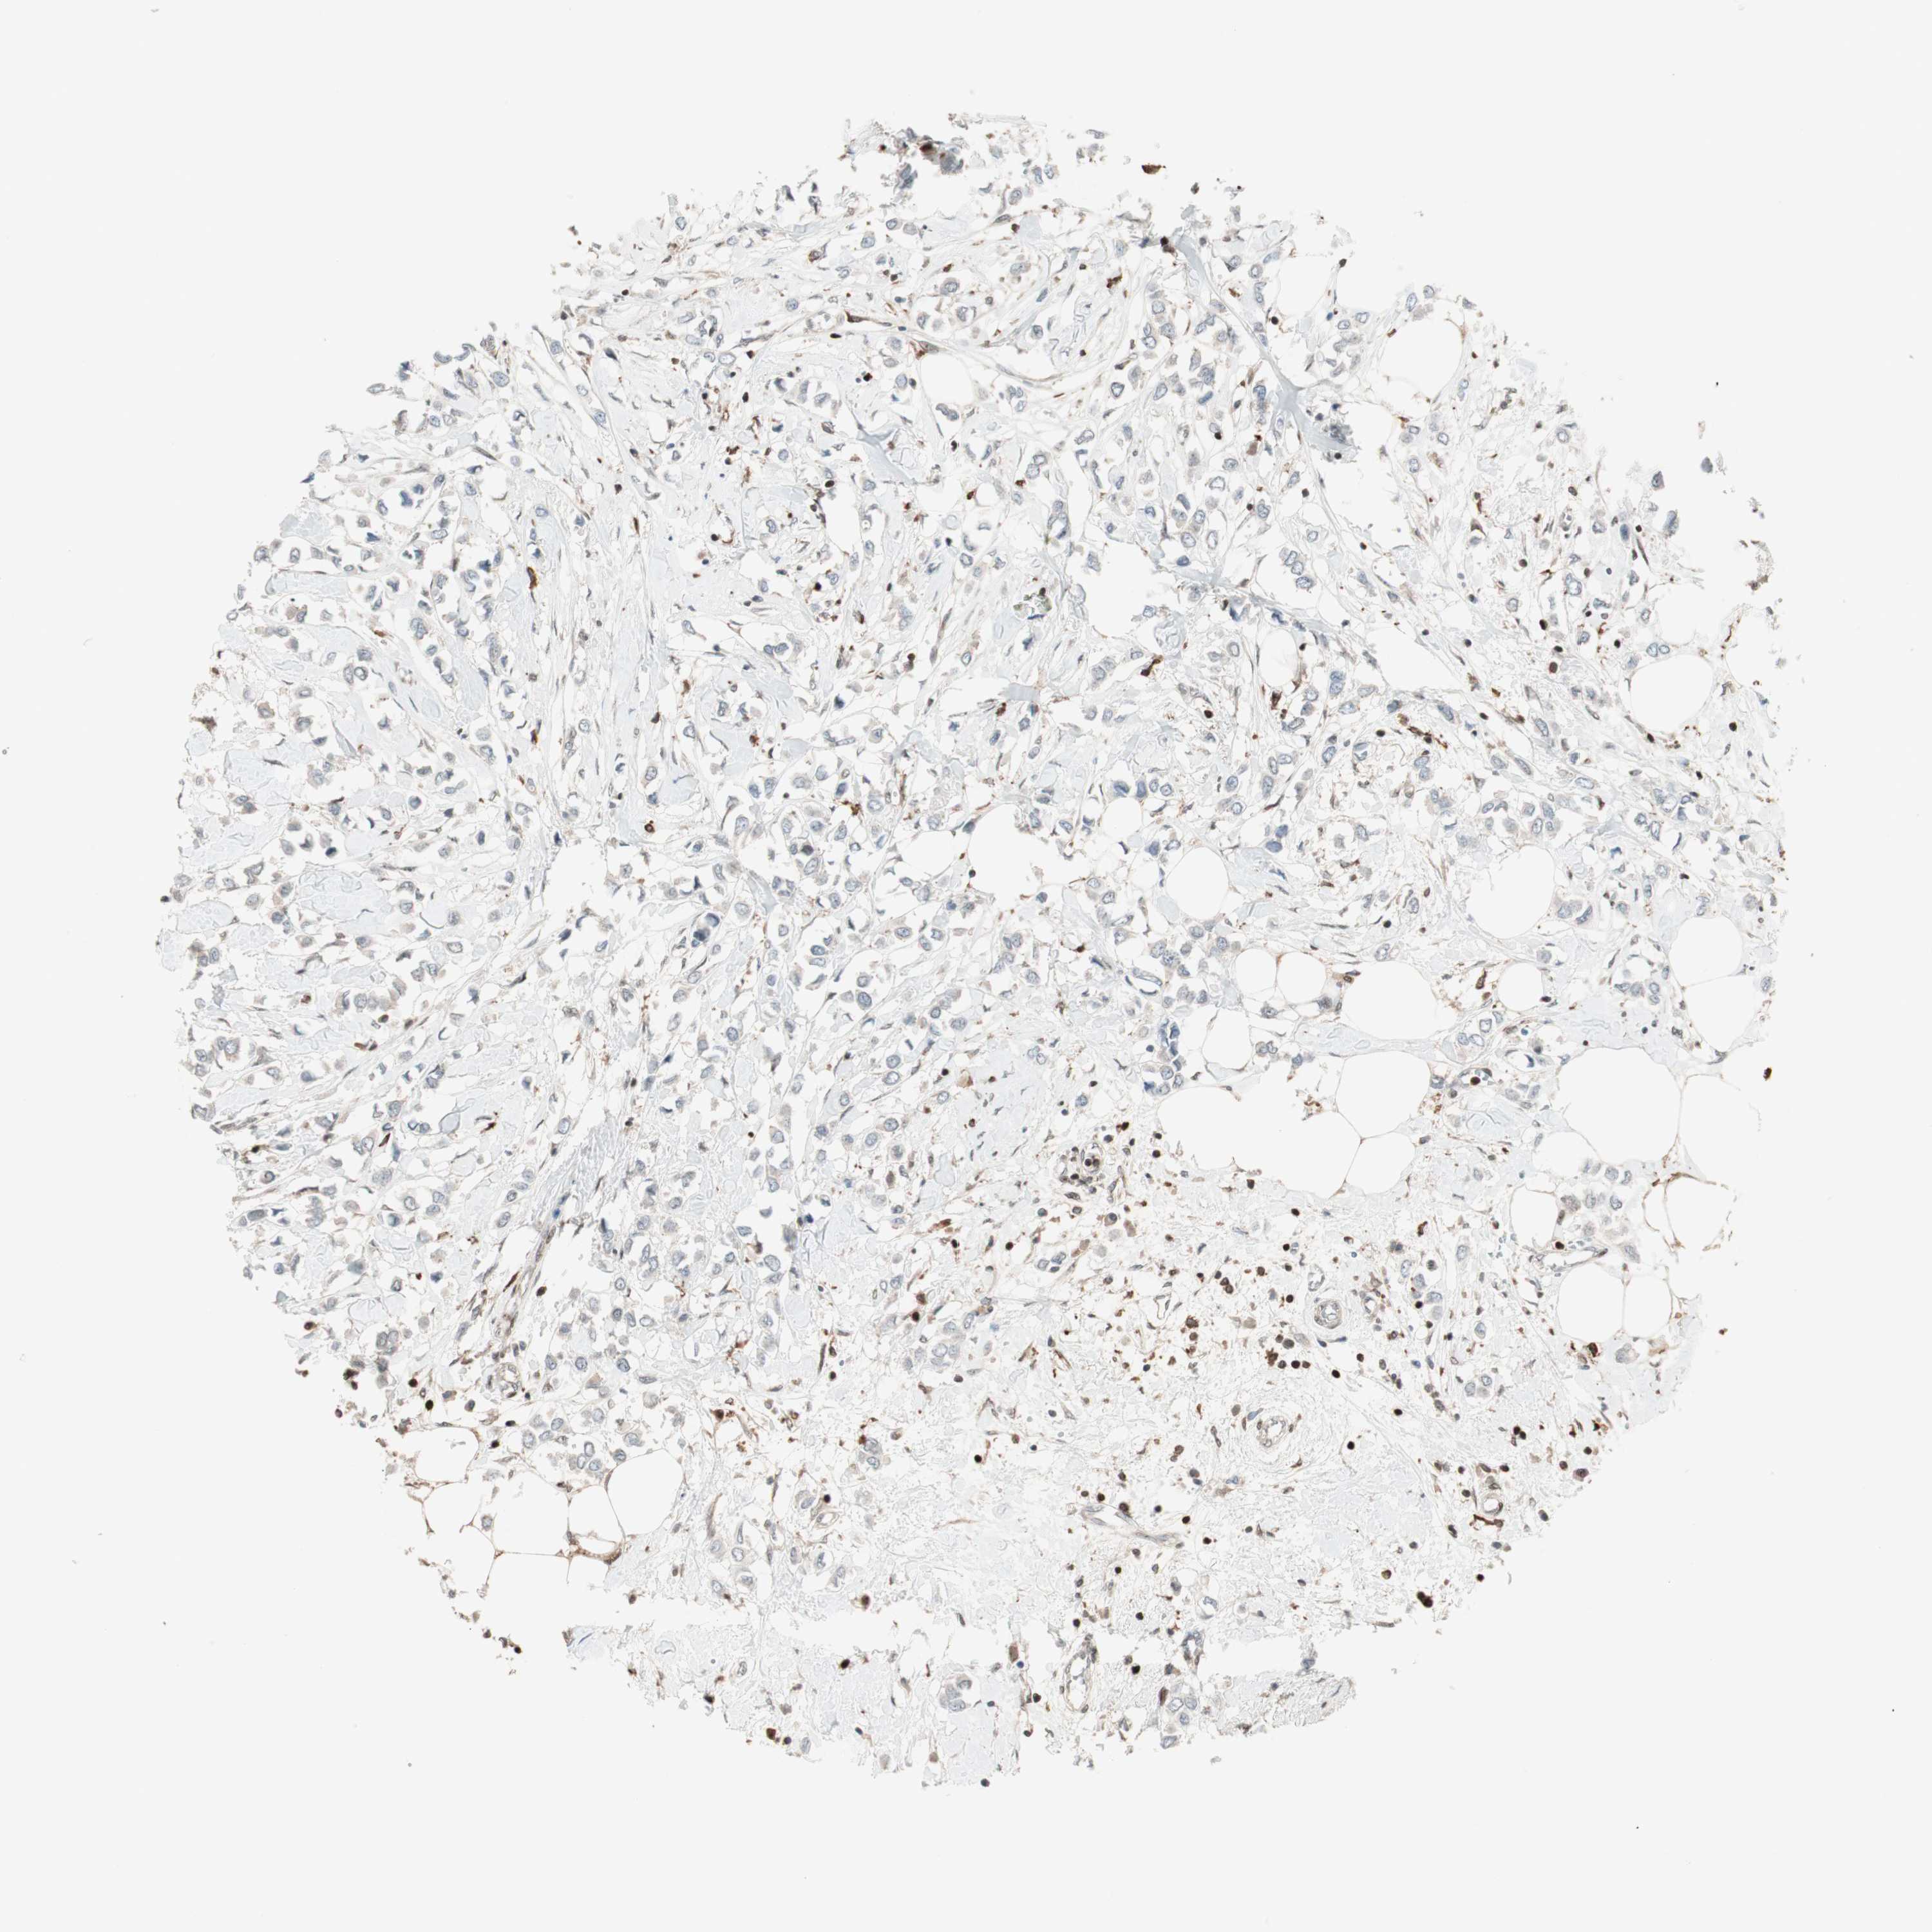

CANCER BREAST CANCER Show tissue menu

BRCA TCGA BRCA VALIDATION PROTEIN EXPRESSION